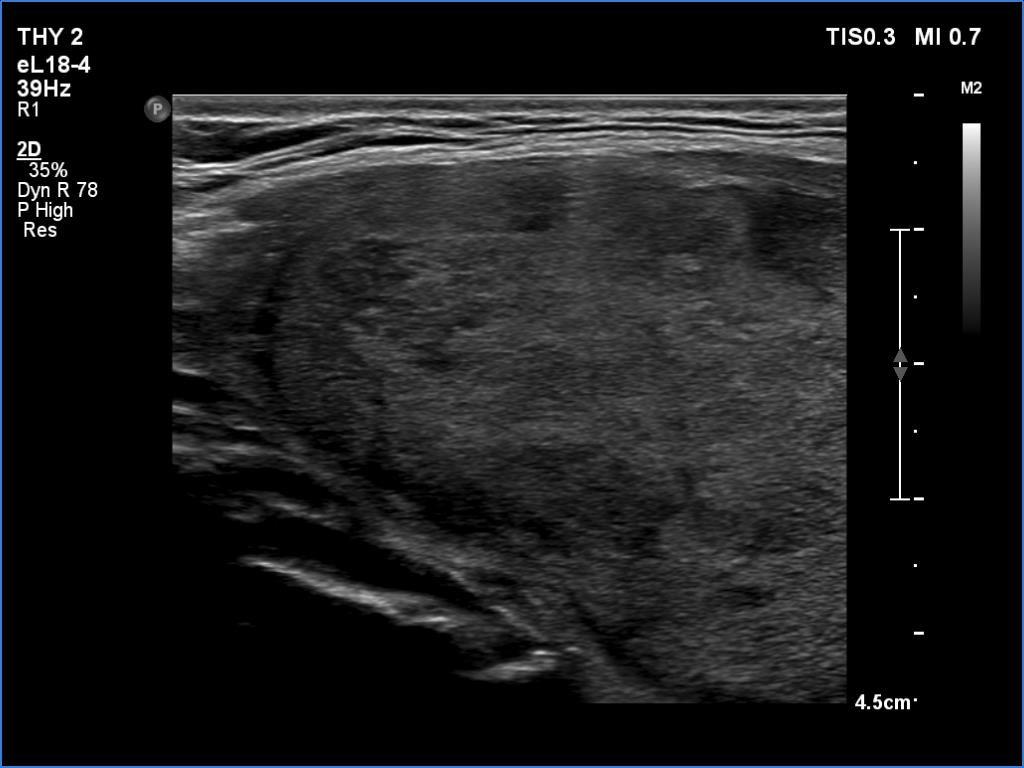

First examination before surgery (first row of images):

Clinical data: A 43-year-old woman requested an evaluation of a thyroid enlargement which was noticed by the patient a month ago.

Palpation: a moderately firm, large nodule in the right lobe.

Laboratory tests: TSH 2.26 mIU/L.

Ultrasonography. A heterogeneous, dominantly echonormal occupied almost the entire right lobe. The lesion had halo and showed both perinodular and intranodular vascularity. The left lobe was intact.

Cytology resulted in oxyphilic tumor.

Right lobectomy was performed. Histopathology: oxyphilic variant of follicular adenoma.